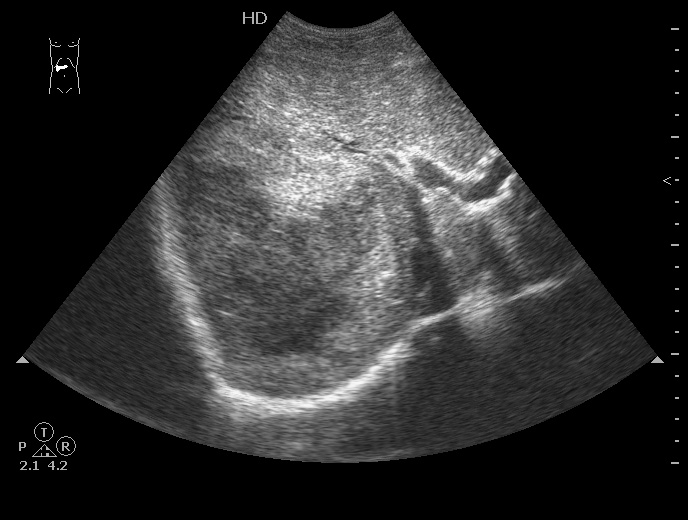

На следующий день сонографическая картина немного изменилась:

Какие мысли?

на узи на абсцесс не похоже, образование солидное ----гепатома?

Гигантская капилярная гемангиома печени.

И дело здесь не в том, что образование уже выявлено , а в том, что бы ответить на два вопроса:

1. Это абсцесс или опухоль?

2. Если опухоль, то доброкачественная она или нет?

Ультразвуковаое контрастирование может помочь в этом.